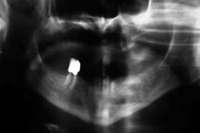

The patient also had extensive bone loss in her anterior mandible (Figure 11).To avoid performing extractions, a simple composite splint was placed between the partial dentures (Figure 12 and Figure 13). The splint reduced the mobility of the teeth and made them less likely to be knocked out during any surgical intubation procedure. As stated earlier, spontaneous osteonecrosis is also possible. Figure 14 shows a had noticed the foreign material, but chose not to act on it. When the material was removed in the dental office (Figure 15 and Figure 16), blood streamed from the nose, so severely that the patient had to be sent to an ear, nose, and throat (ENT) physician. The ENT took a computed tomography scan, which showed a large radiolucency in the upper left quadrant where the foreign material once had been (Figure 17). A review of the radiograph (Figure 18) showed that bone in the maxillary arch had decreased mineral density compared with the mandible. The biopsy report found necrotic bone with organisms consistent with actinomyces. These findings were consistent with biopsies found in the literature.22 When the patient returned for a 1-week follow-up, she still had signs of infection and the site had a foul odor and a discharge (Figure 19). The patient was informed that she should follow up with the ENT and return to the dental office after the infection had been resolved.

Figure 16 Necrotic bone. Figure 17 CT scan showing extensive bone loss. Figure 18 Panoramic radiograph showing decreased bone density.